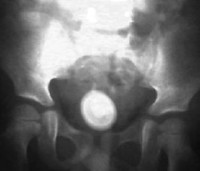

Entre estos últimos se contaba, por supuesto, Civiale, un francés nacido en Auvillac en 1792 que iba a demostrar al mundo los beneficios de la litotricia (extirpación no invasiva de fragmentos de cálculos percutidos) sobre la violenta litotomía de Maisonneuve, y que terminaría por convertirse en el creador del primer servicio de urología del mundo, en el Hospital Necker de París.

El joven Gentile se debatía entre el espanto que le producían las crónicas quirúrgicas de la época y la seguridad que su médico le había transmitido al hablarle del método que había ideado. Civiale había construido una sonda capaz de llegar hasta la vejiga. En su extremo, añadió una pinza que se podía abrir a distancia con un tornillo. Con ella podría sujetar la piedra y luego fragmentarla mediante un sistema de taladro a través de la sonda. Los aparatos utilizados tenían formas inusitadas: tenían que estar compuestos de materiales suficientemente flexibles y, a un tiempo, duros, y seguramente reposaban junto a la mesa de operaciones como extraños artefactos más propios de un carnicero. Era el último grito en tecnología médica, la vanguardia de un siglo con más sombras que luces en el terreno de la cirugía.

Gentile se sometió a tres intervenciones. A todas acudía andando y de todas salía por su propio pie. Civiale sorprendía así a la comunidad médica con una técnica quirúrgica menos invasiva, sangrante y dolorosa, 22 años antes de que se aplicara –en el ámbito de la medicina– la primera anestesia moderna por aspiración de gases.